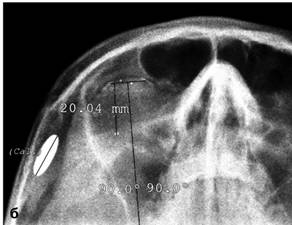

Рентгенологическое исследование глаза с протезом

Комберга-Балтина

Выполняется для определения локализации

инородных тел. Протез Комберга-Балтина представляет собой контактную линзу со

свинцовыми метками по краям протеза. Снимок производят в носоподбородочной и

боковой проекциях при фиксации взора на точке, находящейся прямо перед глазами.

Локализацию инородных тел по снимкам осуществляют с помощью схем-измерителей

(рис. 3).

Рис. 3. Рентгенограммы глазного яблока с

протезом Комберга-Балтина (тонкая стрелка) в боковой (а), аксиальной (б)

проекциях. Инородное тело глазницы (толстая стрелка)